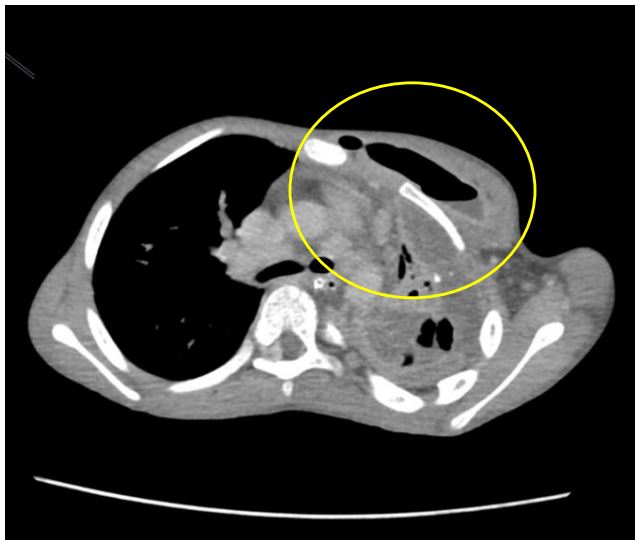

Figure 3: Plain CT coronal image highlighting the calcifications (yellow circles) within the abscesses.by calipers.

We present a case of P.M. An 11-year-old who initially presented with a three-week history of cough, Intermittent fever, and dyspnea. The initial diagnosis of left congenital diaphragmatic hernia was suspected from the chest radiograph and ultrasound in another institution as an opacified left hemithorax and bowel loops within the left thoracic cavity were found, respectively. The patient was subsequently referred to our institution where chest radiograph (Figure 1), chest ultrasound (Figure 2) and contrast-enhanced CT scan of the chest and upper abdomen (Figure 3-7) were done showing left perinephric and left psoas abscesses with intra-thoracic extension, probably through a left diaphragmatic defect, forming empyema thoracis and empyema necessitans. Culture of abscess fluid yielded no bacterial growth but GenExpert test was positive for M. tuberculosis.